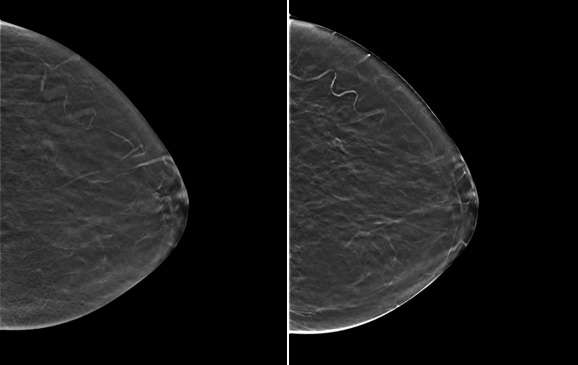

Figure 1. Examples of 2D mammography (left) and synthetic 2D mammography (right).